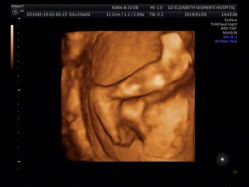

• -郑州万安妇产医院

相册

婉婉777 上传于 18-12-31 | 报错